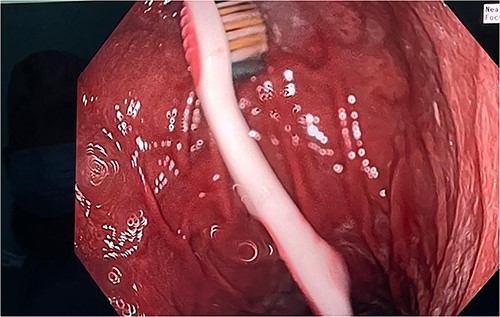

A 25-year-old female presented to the accident and emergency department with a history of accidentally ingested toothbrushes. The patient had a history of anorexia nervosa with multiple episodes of induced emesis. On presentation 3 hours post-ingestion, she was asymptomatic and vitally stable, with no physical abdominal findings. X-ray abdomen was ordered, which confirmed the presence of the toothbrush at the left upper quadrant (Fig. 1). The patient was counselled, and written consent was obtained for an upper oesophagogastroscopy extraction and possible surgery in case of failure of the initial procedure. The procedure was performed while the patient was under general anaesthesia, and the toothbrush was found at the fundus of the stomach (Fig. 2). It was extracted fully via a gastric balloon grasper by grasping the toothbrush from the head. A follow-up upper oesophagogastroscopy was conducted with no evidence of mucosal injury to the stomach or oesophagus. The procedure lasted for ~20 minutes. The patient was discharged after 6 hours and was referred to the psychiatry clinic for further assessment.

In most cases, the preferred extraction tool was a basket or polypectomy snare. However, in our case report, we used a gastric balloon grasper to remove the toothbrush (Fig. 3). This had to be done by a skilled gastroscopist. It is wise to alter the position of the toothbrush such that it is in precise alignment with the oesophagus so that it can pass through the gastro-oesophageal junction. When the oropharynx is reached, it is wise to extend the head and use direct vision. In our case, manual manipulation was used to withdraw the toothbrush completely. In the possibility of extraction failure, it is preferred to be removed surgically, either laparoscopically or open surgery, depending on the surgeons’ experience and preference.